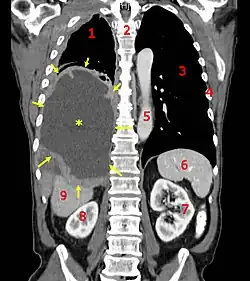

![]() Tomografia komputerowa - jeden ze skanów wykazuje (żółte strzałki) obecność międzybłoniaka opłucnej.1 - prawe płuco, 2 - kręgosłup, 3 - lewe płuco, 4 - żebra, 5 - aorta, 6 - śledziona, 7 - lewa nerka, 8 - prawa nerka, 9 - wątroba | |